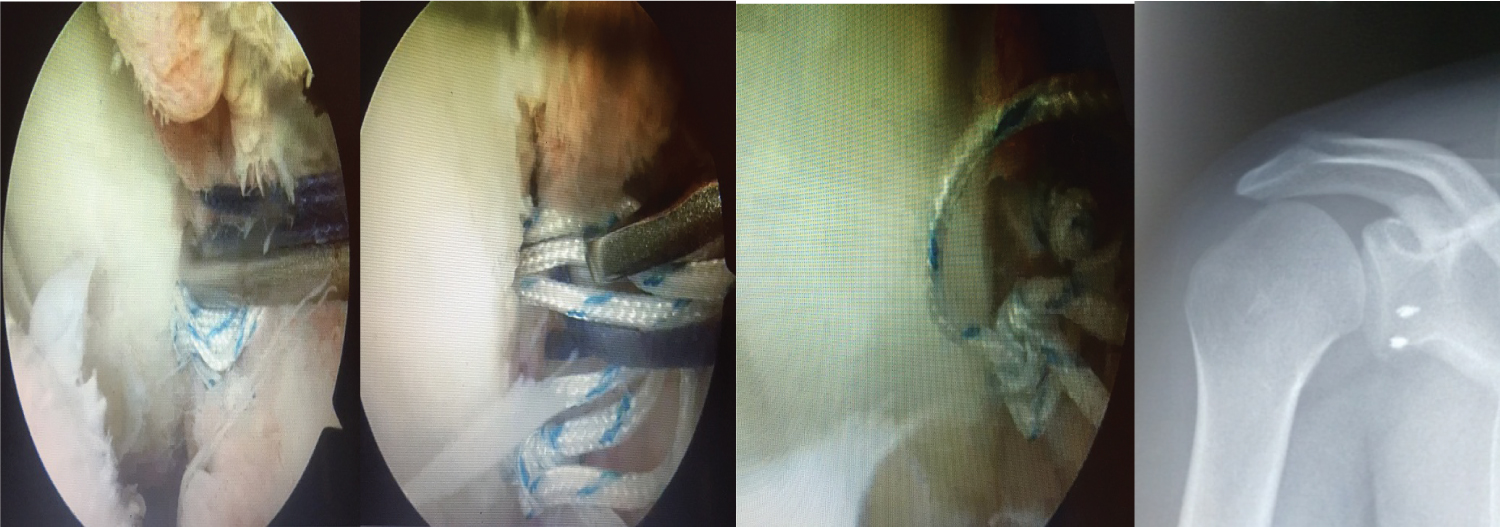

After clinico-radiological evaluation, the therapeutic decision based on the ISIS score, established between 1 and 2 for all cases, was to perform an arthroscopic BANKART. After exploration, the procedure consisted of assessing the presence of a HILL SACKS lesion, which was noncommittal in all cases, and did not require a filling procedure. The anterior-inferior labral detachment and the capsule were then fixed at the anterior glenoid rim at around 15 and 17 o'clock using metal anchors after the anteroinferior edge had been raised (Figure 2 and Figure 3). It should be noted that the patients had no associated lesions on the rest of the labrum.

Figure 3: Tightening of the anchor knot, Two anchors placed at 15 and 17 o'clock of the glenoid rim, Reinsertion of the anteroinferior labrum by two anchors, Radiological control of the anchor location. View Figure 3